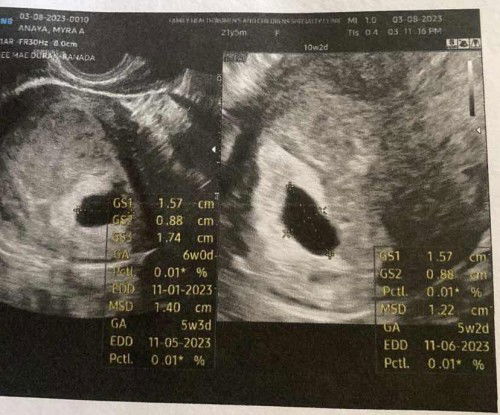

Anembryonic pregnancy

1st ultrasound may gestational sac na nag wait 2 weeks para makita si baby pero yan po lumabas wala pa sya huhu wait pa daw 1 week 😭 thankful if Meron pag wala kailangan tanggapin 🥹😭😭 1st pregnancy

5weeks and 3days base sa size ng bahay bata po 😭